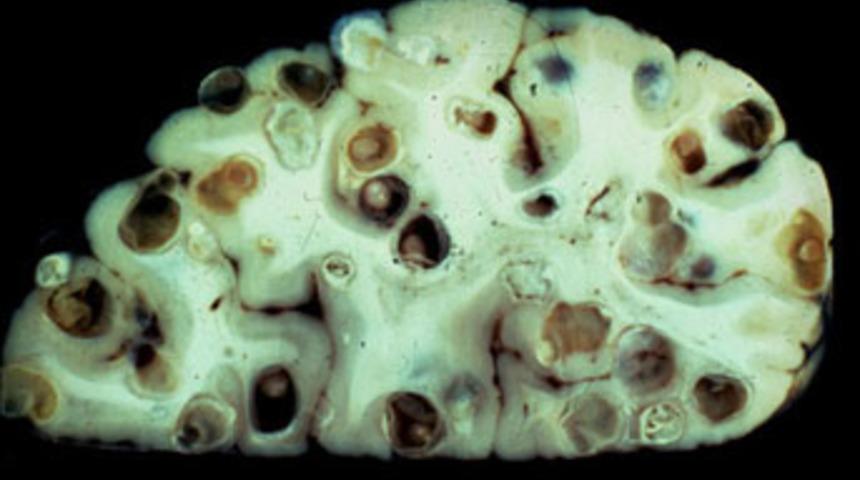

Ancak solucanlar yetişkinliğe ulaşmadan önce büyük kistlerin içinde larva olarak yaşıyor ve bu larvalar daha sonra vücutta hareket ederek beyne yerleşebiliyor.